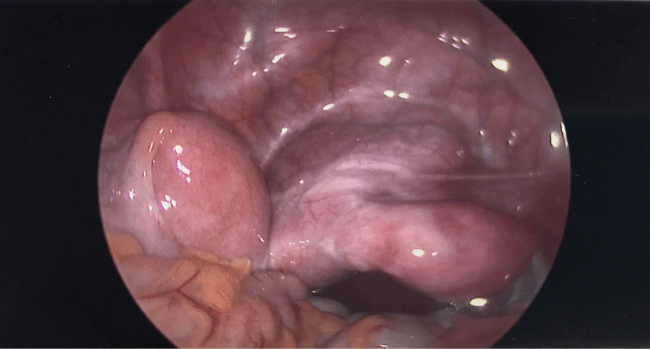

Under direct visualization with laparoscopy, two distinct uterine horns were visualized. The right horn and right fallopian tube appeared normal. The left horn appeared elongated and larger with a dilated left fallopian tube. Normal appearing, post-pubertal ovaries were seen bilaterally. The left fallopian tube was noted to be blocked and had adhesions to the uterus, the left pelvic sidewall, and the large bowel (Figure 4). These adhesions were lysed. Endometriotic implants were present along the serosa of the left uterine horn and were fulgurated.

Subsequently, hysteroscopy was performed. At time of hysteroscopy, the dilators were easily inserted with the curve to the right. The hysteroscope was inserted through a midline cervix, which centered into a normal right uterine cavity. No damage from the dilators or hysteroscope was noted. The right tubal ostium was visualized and appeared normal. When the hysteroscope was placed in the cervical canal, a communication was observed from the left uterine horn into the cervix with drainage of blood into the cervical canal (Figure 5).